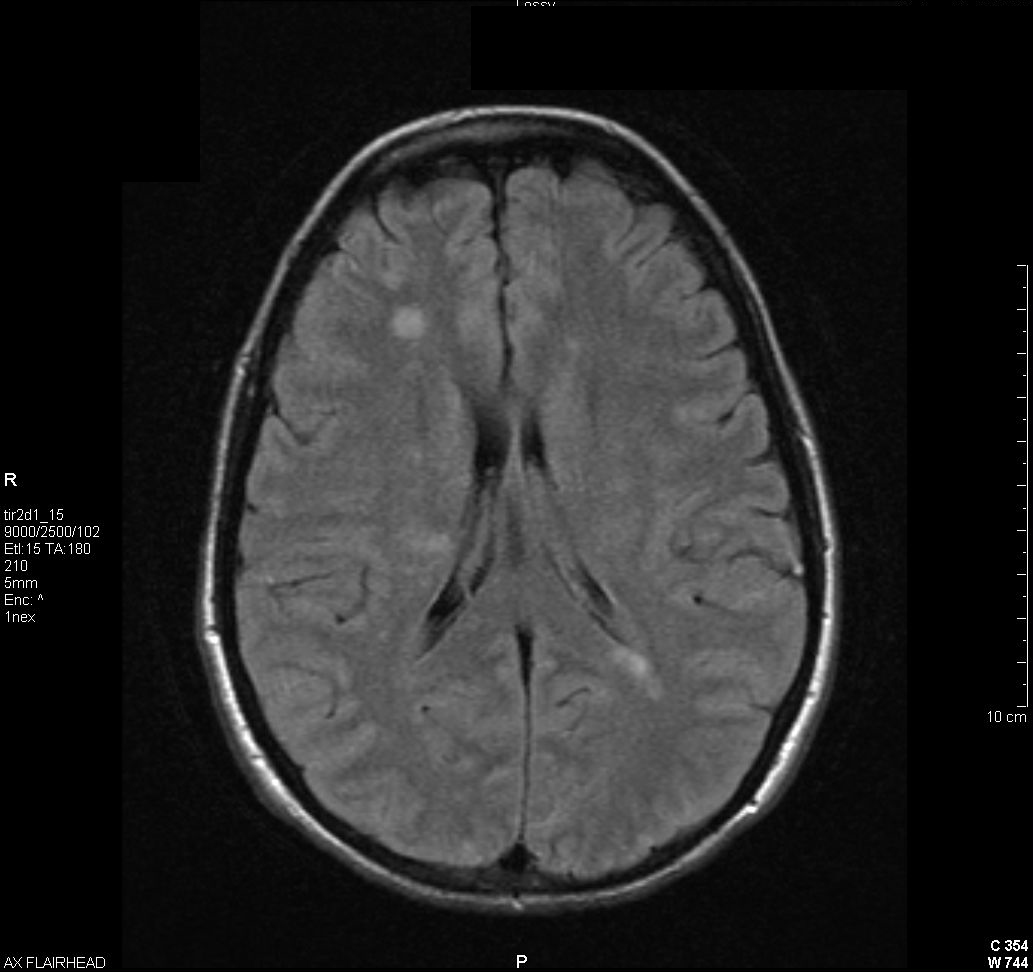

Echocardiography demonstrated a15mm x 10mm mobile, subvalvular vegetation involving the papillary muscles of the posterior mitral valve leaflet. (see video showing mitral valve vegetation) Despite antibiotic treatment, she developed confusion and blurred vision with associated headache and photophobia. An ophthalmologic examination disclosed bilateral uveitis and MRI of the brain demonstrated numerous bihemispheric lesions consistent with septic emboli (figure 1).